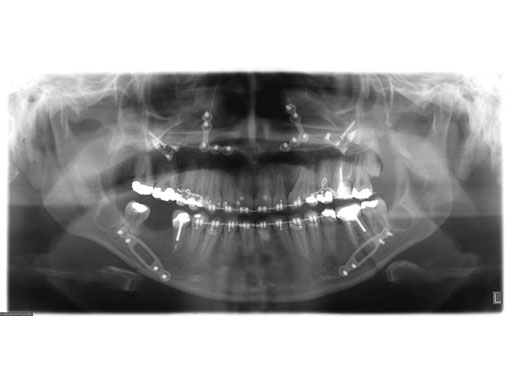

Lefort I maxillary osteotomy, bilateral sagittal osteotomies, and a genioplasty, all fixed with matrix orthognathic system used in a 19-year-old female with significant skeletofacial deformity including maxillary hypoplasia, mandibular excess, and laterognathia.

Fig 2a-c Postoperative images.

Case provided by Daniel Buchbinder, New York, USA